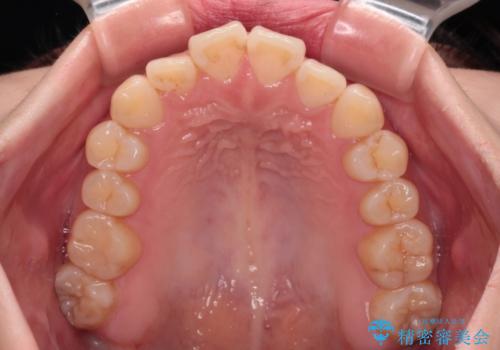

上下非接触の前歯 口元の突出感を改善する抜歯矯正

- 口元の突出感と上下前歯のズレを気にして来院された患者様です。

舌の突出癖により上下の前歯は非接触となっている状態でした。

上下左右の第一小臼歯4本を抜歯し、ワイヤー装置にて矯正治療を行うこととしました。

舌のトレーニングをしっかりと行ってくださり、1年半という非常に短い期間で仕上げることができました。